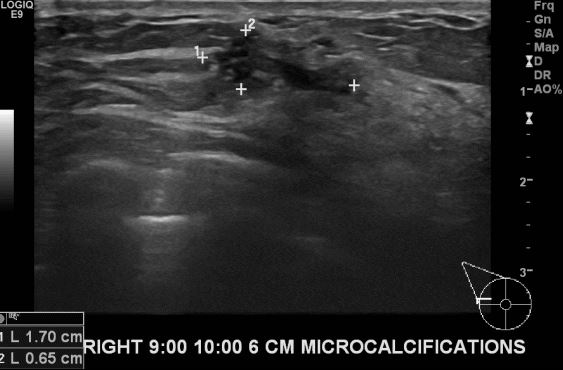

상기환자 우측에 만져지는 멍울로 내원하신 50대 여성 분으로 우측 9시~10시 방향에서

6cm떨어진 거리에 만져지는 멍울 조직검사 시행하여 우측 유관암 진단되었습니다.